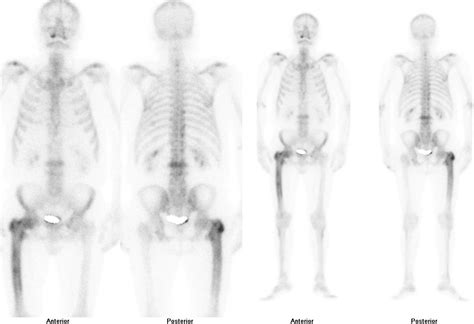

• Imaging tests: X-rays, CT scans, MRI, and bone scans can help visualize the affected bones and assess the extent of the disease.